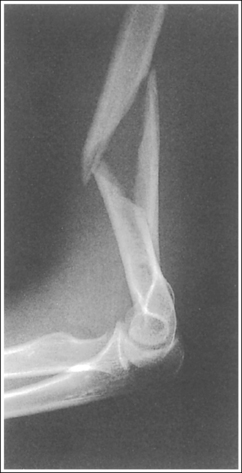

See Figure 4-76 and Box 4-20.

Contrast and density are adequate to demonstrate the anterior, posterior, and supinator fat pads, surrounding soft tissue, and bony structures.

• Fat pads on lateral elbow projection. To evaluate a lateral elbow projection, the reviewer not only analyzes the bony structure, but also studies the placement of the soft tissue fat pads. Three fat pads of interest are present on a lateral elbow projection, the anterior and posterior fat pads and the supinator fat stripe. The anterior fat pad should routinely be seen on all lateral elbow projections when adequate exposure factors are used. This pad is formed by the superimposed coronoid process and radial pads and is situated immediately anterior to the distal humerus (Figure 4-77). A change in the shape or placement of the anterior fat pad may indicate joint effusion and elbow injury. The posterior fat pad is normally obscured on a negative lateral elbow projection because of its location within the olecranon fossa. When an injury occurs, joint effusion pushes this pad out of the fossa, allowing it to be visualized proximal and posterior to the olecranon fossa. The supinator fat stripe is visible parallel to the anterior aspect of the proximal radius (see Figure 4-77). Displacement of this fat stripe is useful for diagnosing fractures of the radial head and neck.

The elbow is flexed 90 degrees.

• When the elbow is flexed 90 degrees, the forearm can be elevated to align the anatomic structures of the distal humerus properly, and displacement of the anterior and posterior fat pads can be used as signs to determine diagnosis. If the elbow is not adequately flexed, these fat pads can be displaced by poor positioning instead of joint pathology, interfering with their diagnostic usefulness. When the arm is extended, nonpathologic displacement of the anterior fat pad results from intraarticular pressure placed on the joint. Nonpathologic displacement of the posterior fat pad is a result of positioning of the olecranon within the olecranon fossa, which causes proximal and posterior displacement of the pad (see Image 87).

The elbow is in a lateral projection. The distal humerus demonstrates three concentric arcs, which are formed by the trochlear sulcus, capitulum, and medial trochlea. The elbow joint space is open, and the radial head is superimposed over the coronoid process.

• A lateral elbow projection is obtained when the humeral epicondyles are positioned directly on top of each other, placing an imaginary line drawn between them perpendicular to the IR. To obtain this humeral epicondyle positioning, place the humerus parallel with the IR and elevate the distal forearm until the palpable medial and lateral epicondyles are superimposed (Figure 4-78). This positioning aligns the trochlear sulcus, capitulum, and medial trochlea into three concentric (having the same center) arcs (Figure 4-79). The trochlear sulcus is the small center arc. It moves very little when a positional change is made and works like a pivoting point between the capitulum and medial aspect of the trochlea. The largest of the arcs is the medial aspect of the trochlea. It is demonstrated very close to and slightly superimposed on the curve of the trochlear notch. The intermediate-sized arc is the capitulum. When these three arcs are in accurate alignment, the elbow joint is visualized as an open space and the anterior and proximal surfaces of the radial head and coronoid process are aligned.